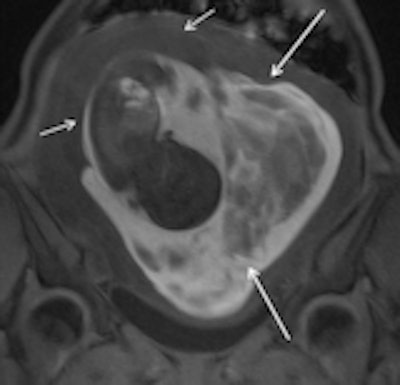

Subchorionic hemorrhage due to placenta abruption in a 30-year-old woman at 29 weeks gestation presented with acute pelvic pain and vaginal bleeding. Left: Coronal T1-weighted gradient-echo image (4.1/1.1, 10° flip angle) shows a large, hyperintense subchorionic hematoma (arrows). Middle and right: The intrauterine hematoma is mildly hyperintense to placenta on the sagittal T2-weighted half-Fourier RARE image (1000/90) (Middle) and markedly hyperintense to placenta on the sagittal diffusion-weighted image (b value, 800 sec/mm2) (right). Note the hematoma has hypo- and hyperintense areas, due to repeated bleeding. Short arrows indicate the placenta. All images courtesy of Dr. Gabriele Masselli.Masselli and colleagues on the ESUR Female Pelvic Imaging Subcommittee sought to develop guidelines for the appropriate imaging of acute abdominal and pelvic pain in established intrauterine pregnancy based on a detailed literature review and consensus expert opinion.